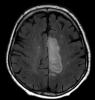

Valorado en urgencias por clínica de debilidad facial izquierda. Comenzó tto con corticoides sin mejoría.  Refiere alteración cognitiva, con despistes y pérdida de memoria desde el día siguiente,...

Neurología: InfecciosasEtiología: Infecciosas / inflamatoria / desmielinizanteDiagnóstico final: leucoencefalopatía multifocal progresivaNivel de certeza: